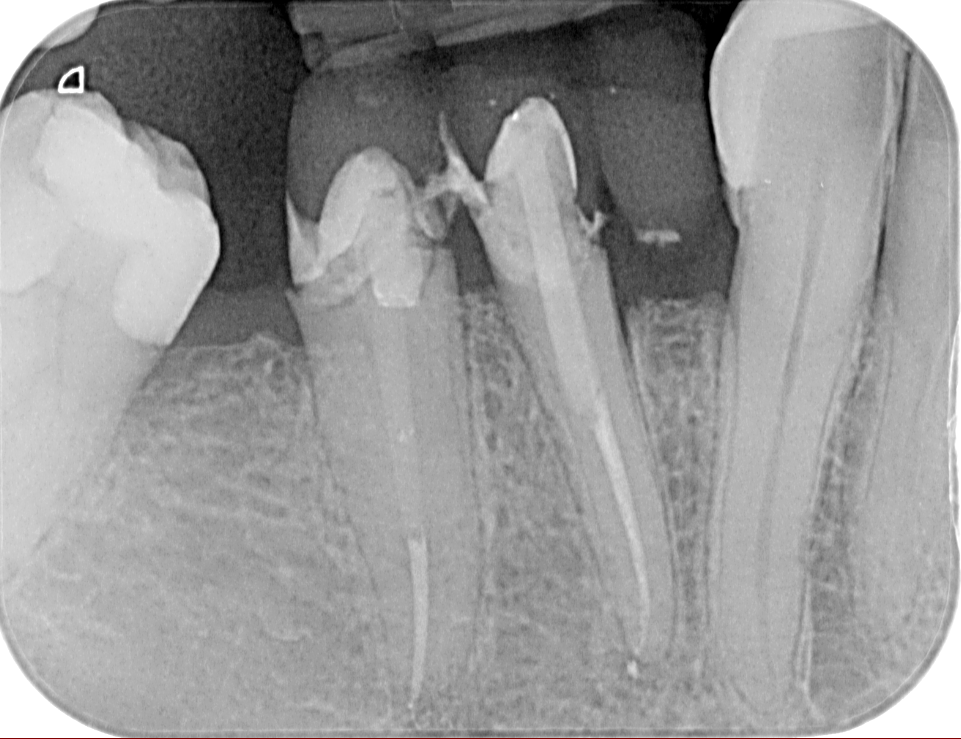

Ενδοδοντία (Απονευρώσεις)